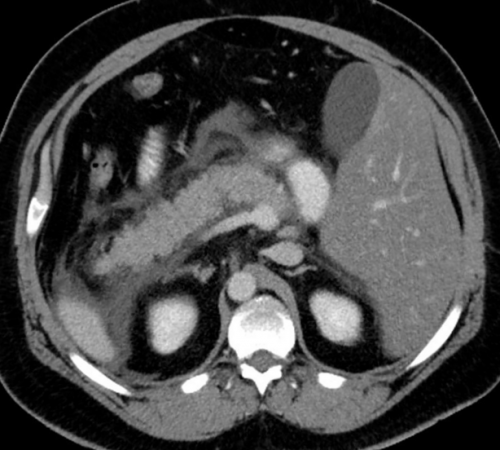

рентген, УЗИ, КТ или МРТ, ЭРХПГ, эндоскопическая ультрасонография. Данные анализы позволяют <

• Визуализирующие обследования. Это может быть

Диагноз ставится на основании ультразвукового исследования, компьютерной или магнитно-резонансной томографии. В ходе исследования обычно обнаруживаются суженные протоки поджелудочной железы из-за образования в них камней — кальцинатов. Аппаратные методики позволяют также обнаружить кисты на месте атрофированной ткани. Лабораторные анализы крови при хроническом панкреатите мало информативны.